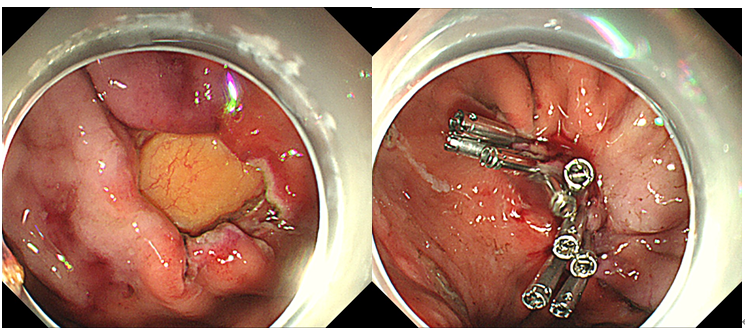

image.png

创面处理:电凝处理出血部位和裸露血管,特别是靠近浆膜侧血管断端,可以借助透明帽辅助显露浆膜侧。确切处理好周缘的血管断端后,确定无出血或渗血后再进行缝合。根据术后创面的大小选择合适的闭合方法,创面较小可用金属夹,创面较大( 直径>1.5~2 cm) ,可采用尼龙绳钛夹荷包缝合技术。本例穿孔面约1cm,选择金属夹直接夹闭缝合创面。